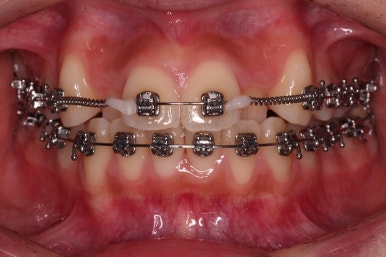

이번 환자분이 선택하신 장치는 엠파워 메탈이라고 하는 자가결찰 금속 장치에요.

메탈 장치라고 모두 구식의 옛날 안좋은 장치라고 생각하시면 안되고, 자가결찰 인지 아닌지 여부가 훨씬 중요하다고 거듭 말씀드렸지요.

자가결찰이기만 하면 치료 효과 동일하며, 단지 성분이 메탈이냐 세라믹이냐에 따라 보이는 정도, 부피, 모양 등이 약간 차이가 있을 뿐이에요.

가지런하게 하면서 안으로 쏙 들어가있는 앞니를 가지런하게 할 자리 확보부터 해줍니다.

자리 확보 이 후에 가지런하게 해주는데요.